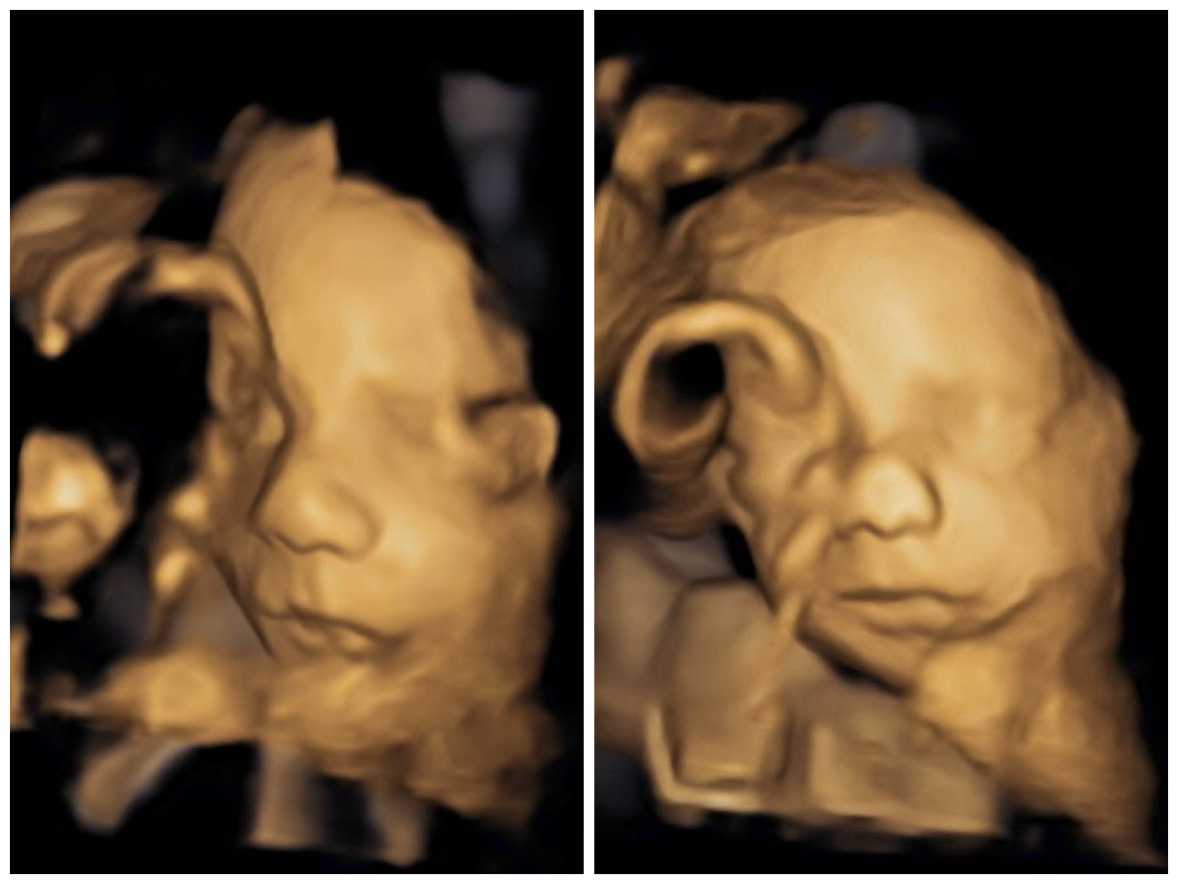

18-week ultrasound (size of a pint of ice cream)

He is still wiggling around SO much! Lots of stretches and thumb sucking. Everything looks great on the anatomy scan! He has daddy's nose!